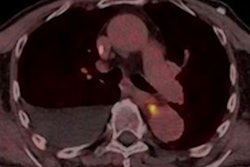

In a patient who had received two months of treatment with pembrolizumab, a PET/CT study showed patchy peripheral consolidations, and the diagnosis was inflammatory pneumonitis. This patient died two months later due to an infectious pneumonia.